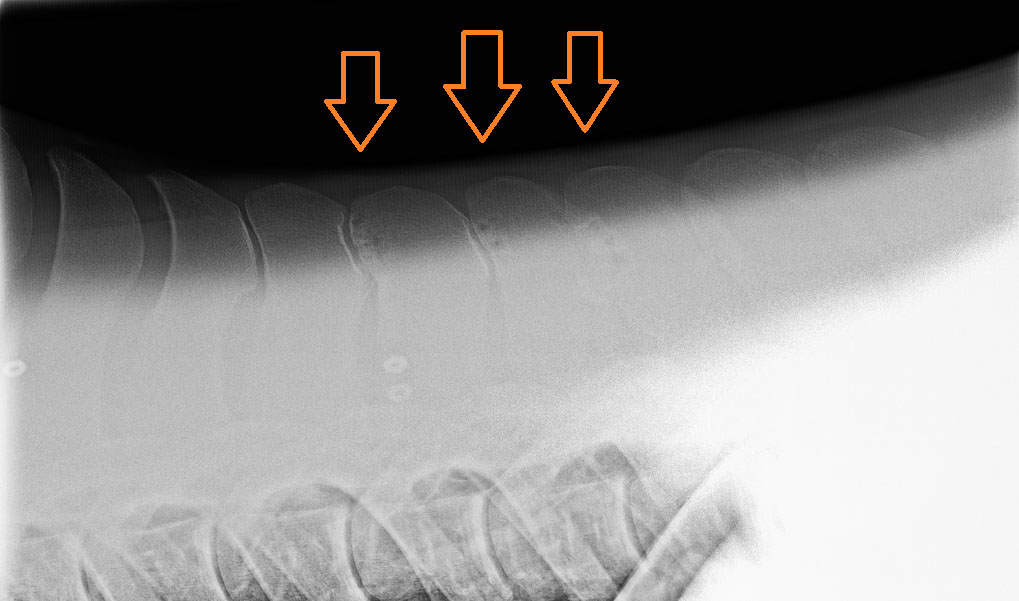

Other modalities you may see your vet use to diagnose kissing spines is infusion of local anaesthetic at the site of the kissing spines identified on radiographs. If this is the primary cause of the problem you should see an improvement of clinical signs. However, infusion of local anesthetic would also show improvement in horses with primary muscular back pain and has even been shown to improve the movement of horses with no clinically identifiable back pain. Your vet may also ultrasound the muscles along the back. Left to right asymmetry of the one the epaxial muscles, the multifidus muscle, has been associated with back pathology (both spinous and muscular). However, this muscle can be difficult to ultrasound and requires experience with the technique. Nuclear scinitgraphy is also an advanced diagnostic modality that is sensitive at picking up active boney changes along the back.

Image above: kissing spine nuclear scinitgraphy image